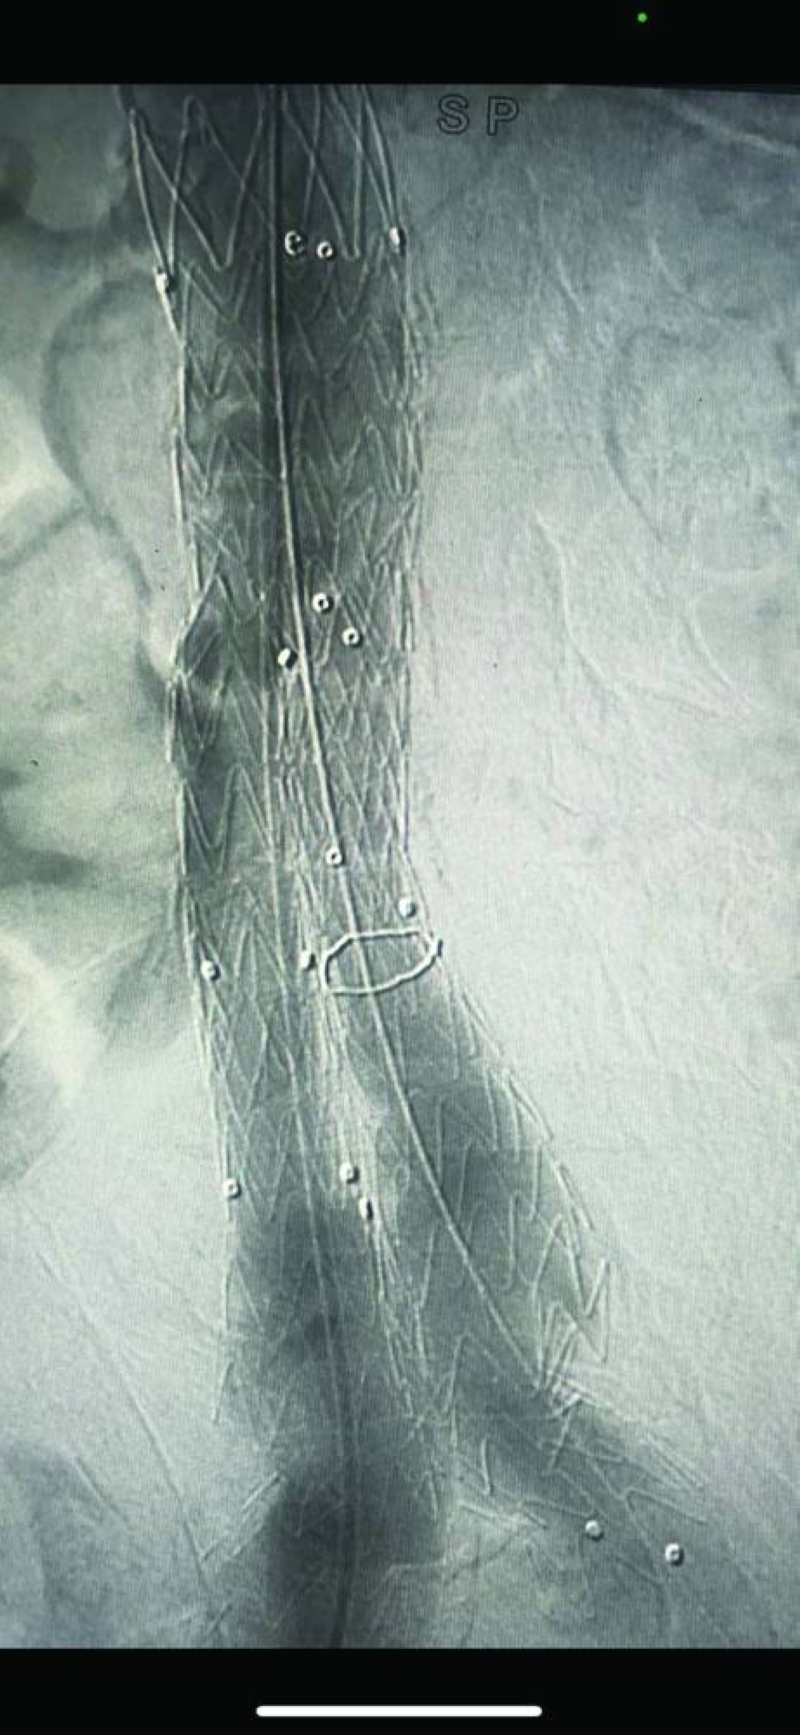

فقد نجح فريق مركز صباح الأحمد للقلب، المكون من استشاريَي القلب والقسطرة في المركز الدكتور نادر عيسى العسعوسي، والدكتور أحمد سعيد طه، في تبديل الصمام الأورطي للمريض بالقسطرة (TAVI) وتركيب دعامات بالشريان التاجي الأيسر والأيمن، فيما تمكن فريق مستشفى مبارك الكبير المكون من استشاري جراحة الأوعية الدموية الدكتور عبدالله الفواز، واستشاري الأشعة التداخلية الدكتور حسين جراغ، من إصلاح تمدد شرياني كبير بالأبهر البطني، كان على وشك الانفجار (EVAR for AAA)، وذلك في آنٍ واحد وبصفة عاجلة، وبدون جراحة لإنقاذ حياة مريض، يقارب عمره من نحو 100 عام، حيث كان المريض قد أُدخِل إلى العناية المركزة القلبية بمركز صباح الأحمد للقلب، في حالة حرجة، وهو يعاني من جلطة بالقلب وارتشاح رئوي حاد، وتجمُّع كبير للسوائل بالصدر (massive bilateral pleural effusion)، مما أدى إلى فشل تنفسي حاد. غير أن حالة المريض بعد هذا الإنجاز الطبي استقرت، وتماثل للشفاء بعد وضعه تحت العناية المكثفة، إلى أن خرج للمنزل في حالة مستقرة.

وقد تدهورت حالة المريضة على مدار سنتين، وأدخلت من الطوارئ إلى العناية المركزة للقلب بالمركز وهي تعاني من صدمة قلبية واحتشاء بعضلة القلب (acute MI and cardiogenic shock) وتجمُّع شديد للسوائل بالجسم (generalized anasarca )، حيث تم إجراء قسطرة تداخلية عاجلة، وتركيب 4 دعامات بالشريان التاجي الأيسر الرئيسي والتاجي الأيمن، تحت الدعم من المضخة القلبية الرئوية (ECMO)، وبعد ذلك تبديل الصمام الأورطي بالقسطرة (TAVI) من قبل فريق تبديل الصمام الأورطي بالقسطرة.

• تبديل الصمام الأورطي للمريض بالقسطرة (TAVI)

• تركيب دعامات بالشريانين التاجيين الأيسر والأيمن

• قسطرة تداخلية عاجلة

• تركيب 4 دعامات بالشريانين التاجي الأيسر الرئيسي والتاجي الأيمن، تحت الدعم من المضخة القلبية الرئوية (ECMO)

• تبديل الصمام الأورطي بالقسطرة (TAVI)